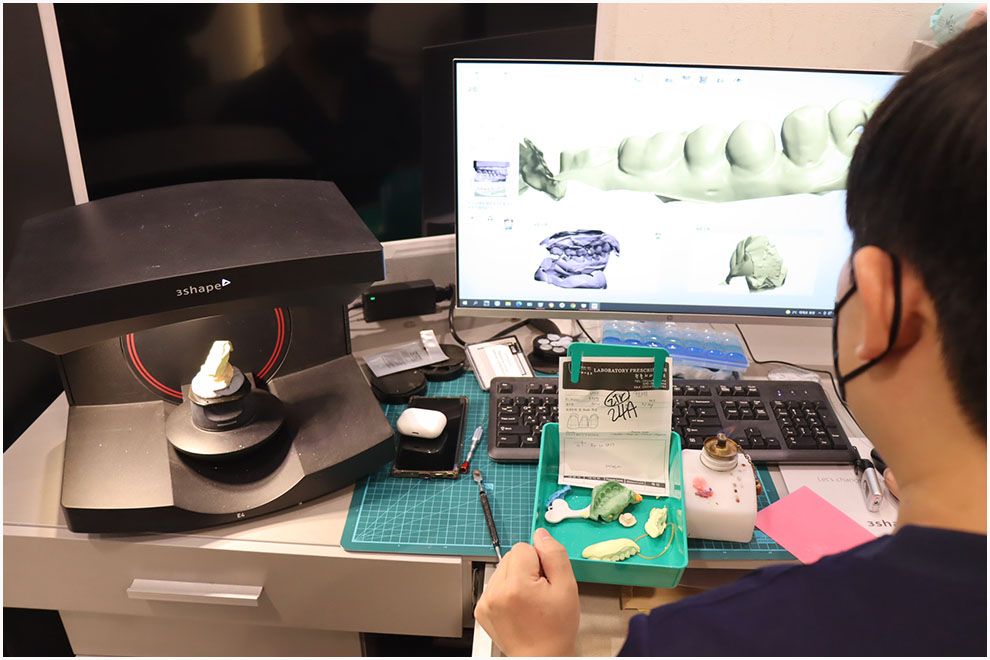

-첨단 장비

최신 디지털 검진 장비와 3D 기술을 활용해 정밀한 진단이 가능한 치과